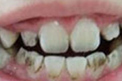

快速解决以下牙齿问题 龅牙、虎牙、老鼠牙、氟斑牙、牙齿拥挤、四环素牙、畸形牙、牙齿稀疏

该术以泰康拜博口腔的3-3-4-4黄金美齿法则漫步在国际齿科美容界,具有快速正畸,美齿、矫正、治齿一步到位的功效。并且,突破 传统美牙冠的弊端,将德国VITA比色术,美国微痛术和口腔内窥镜数码定位有机结合。

技术特点:技术特点:① 高效快速 仅需7天; ② 无需拔牙; ③ 过程舒适; ④ 美齿、矫正、治齿一步到位